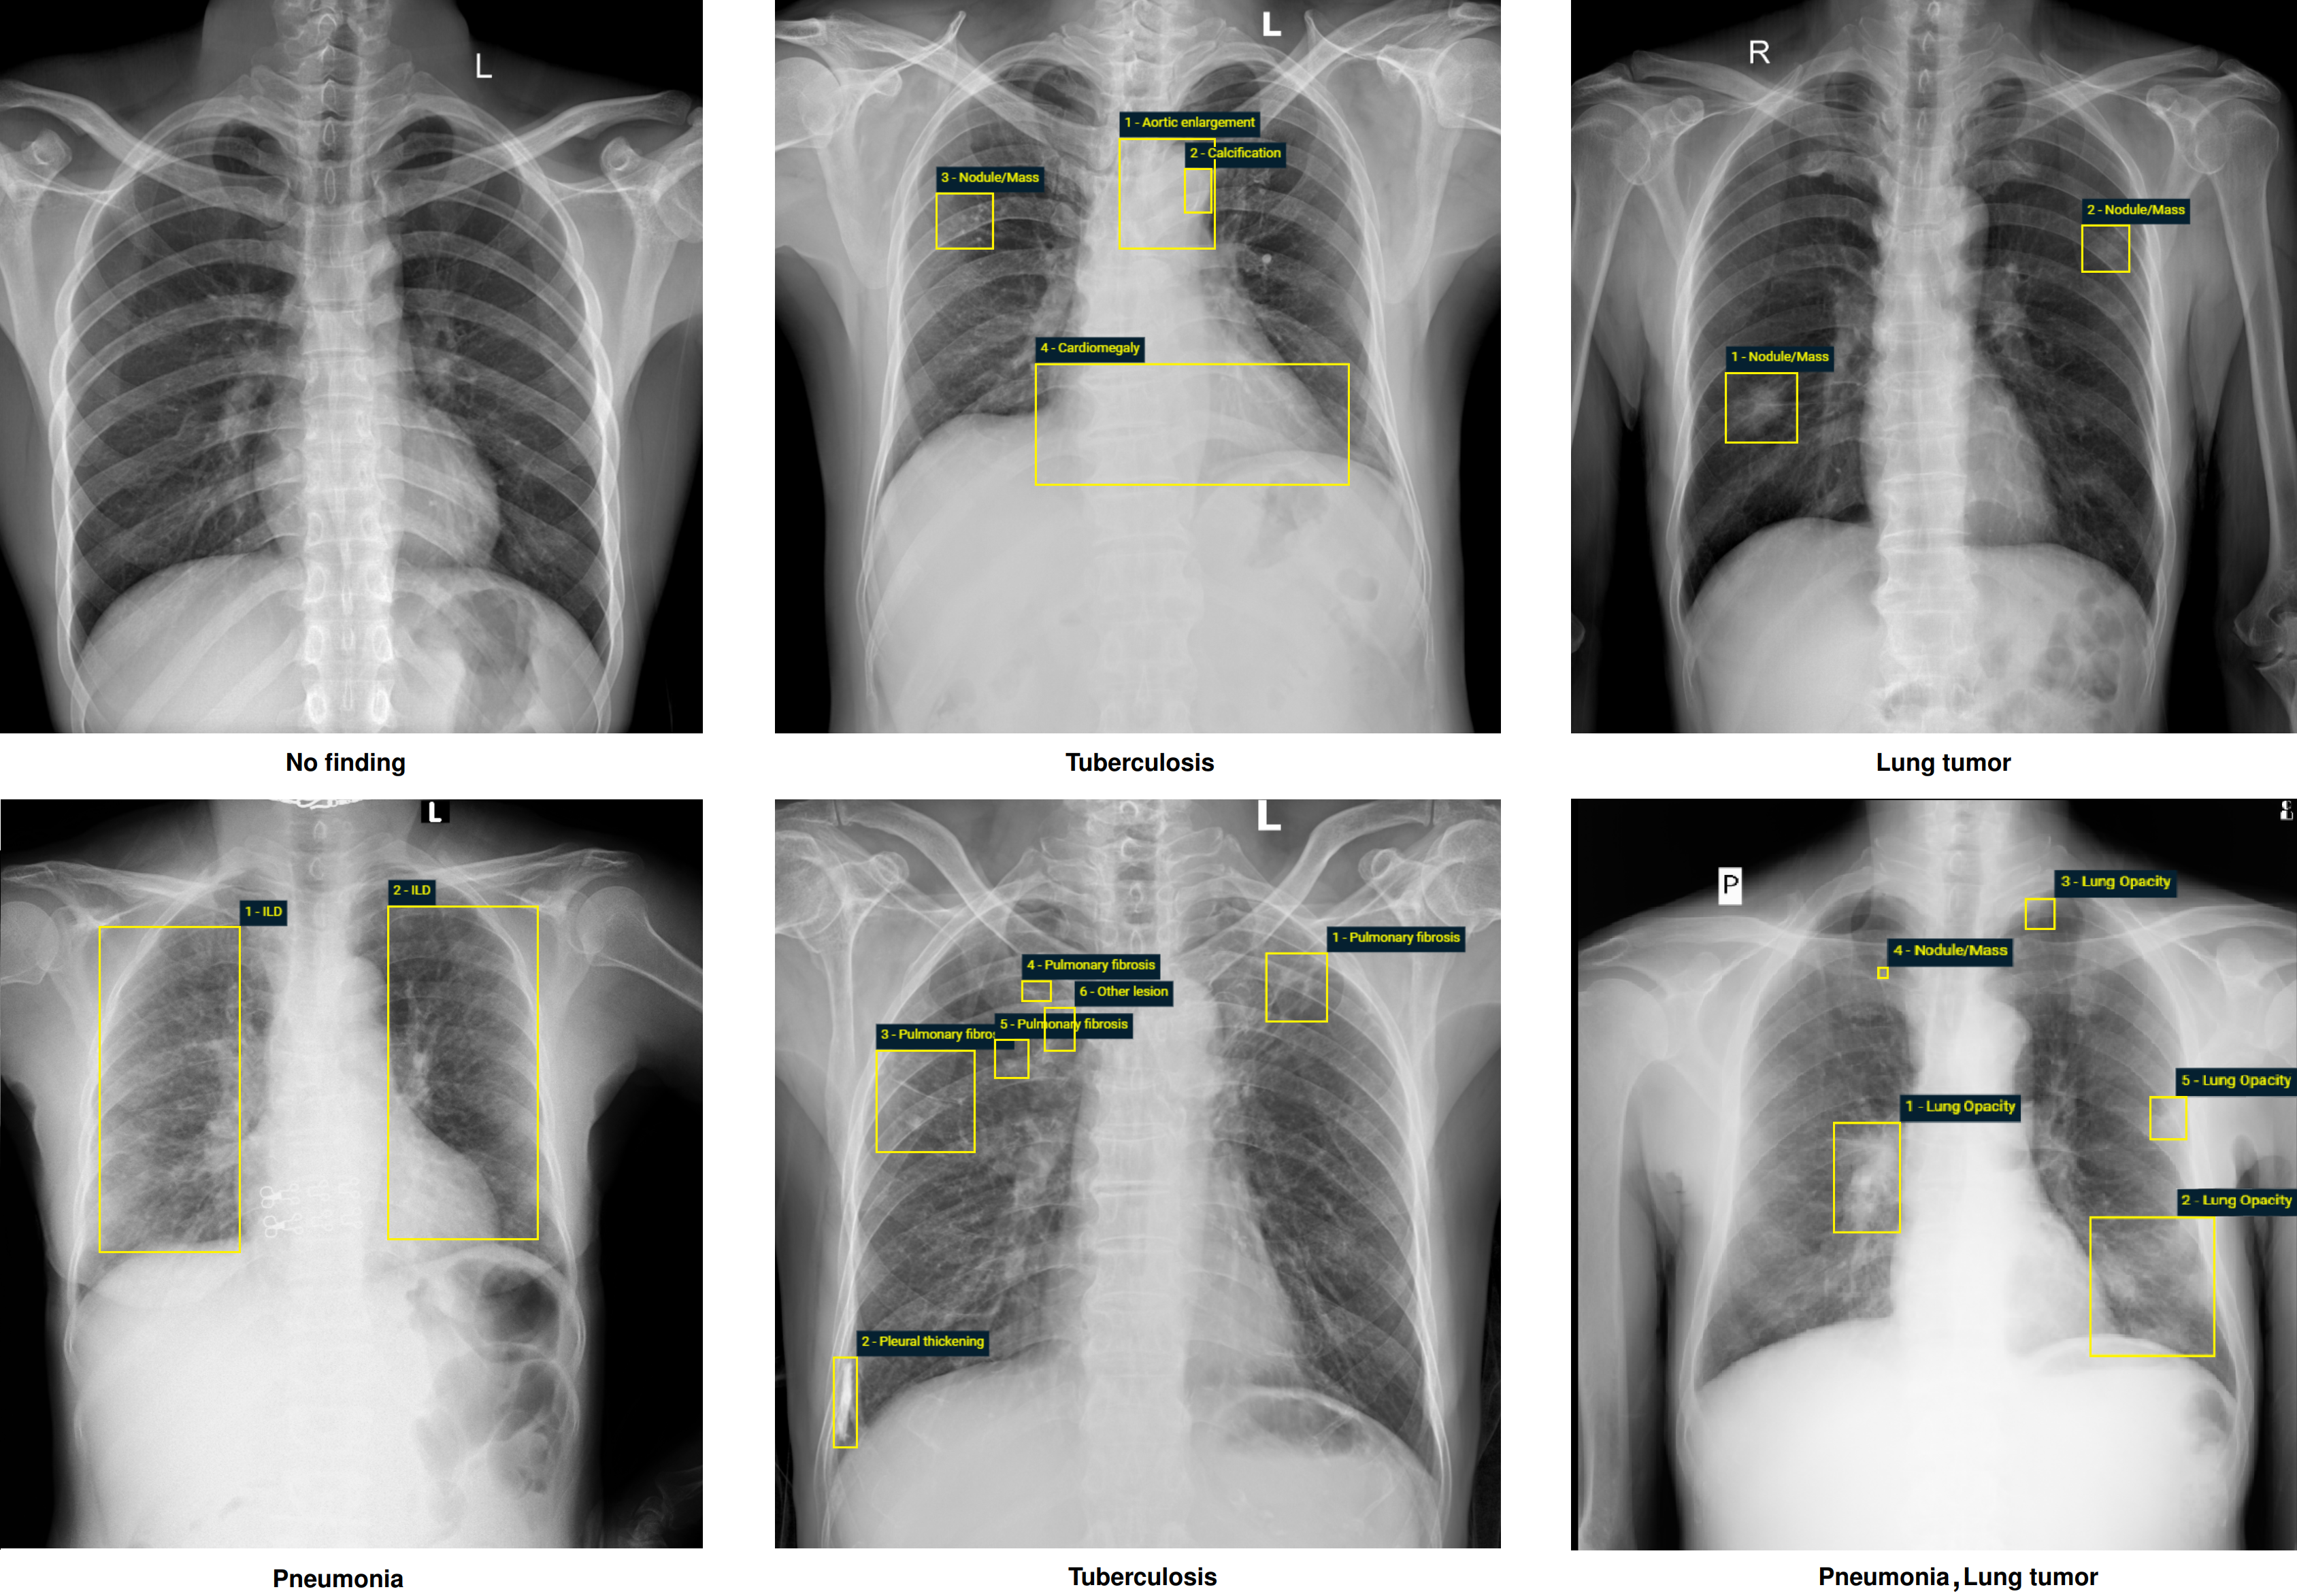

The VinDr-CXR dataset was labeled for a total of 28 findings and diagnoses in adult cases: (1) Aortic enlargement, (2) Atelectasis, (3) Cardiomegaly, (4) Calcification, (5) Clavicle fracture, (6) Consolidation, (7) Edema, (8) Emphysema, (9) Enlarged PA, (10) Interstitial lung disease (ILD), (11) Infiltration, (12) Lung cavity, (13) Lung cyst, (14) Lung opacity, (15) Mediastinal shift, (16) Nodule/Mass, (17) Pulmonary fibrosis, (18) Pneumothorax, (19) Pleural thickening, (20) Pleural effusion, (21) Rib fracture, (22) Other lesion, (23) Lung tumor, (24) Pneumonia, (25) Tuberculosis, (26) Other diseases, (27) Chronic obstructive pulmonary disease (COPD), and (28) No finding. These labels were divided into 2 categories: local labels (1-22) and global labels (23-28). The local labels should be marked with bounding boxes that localize the findings, while the global labels should reflect the diagnostic impression of the radiologist. The definition of each label is detailed in Table 2 (supplementary materials). This list of labels was suggested by a committee of the most experienced radiologists from the two hospitals. The selection of these labels took into account two factors: first, they are prevalent and second, they can be differentiated on CXRs. Figure 3 illustrates several samples with both local and global labels annotated by radiologists.